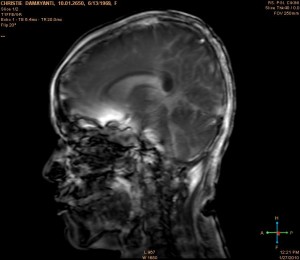

Dan ini adalah otakku waktu itu ( benar2foto otakku ), dilihat kepalaku dibelah ditengah2 hidung sebelah kiri :

Jika keadaan otak yg tidak diserangstroke karena pendarahan, ‘sesuatu’ yg ada di tengah2 otak itu yg berwarna putih, tentulah tidak ada. Coba lihat, kira2 20% otak kiri ku terkena darah ! Aku menderitaserangan stroke akut pada waktu itu.

Coba lihat. Sebuah titk / noktah warna hitam adalah inti dari serangan stroke ku. Disinilah bermula pendaraharan ku. Pembuluh darahku pecah disana. Dan darah merembes sampai 20% otak kiri ku. …..